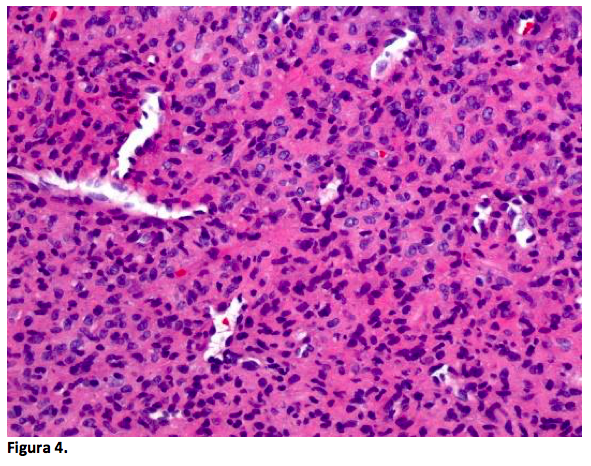

Con estos datos, se planificó la intervención quirúrgica en dos tiempos. En una primera intervención se realizó resección de tumor de región malar izquierda, con separación de rama cigomática del nervio facial y posteriormente, se practicó deslizamiento de colgajo músculo cutáneo para reparación de la herida. Se realizó estudio transoperatorio en el departamento de anatomía patológica, donde se reportó fibrohistiocitoma epitelioide celular con invasión de músculo estriado, multifragmentado (figuras 3,4 y 5), por lo que no fue posible realizar la evaluación de los márgenes quirúrgicos.

Las características histológicas del tumor en este caso son similares a las descritas en la literatura. Se encontró una proliferación de células poligonales con citoplasma eosinófilo abundante, con núcleos redondos vesiculosos, con presencia de algunas células binucleadas y muy escasas células multinucleadas, además de mitosis aisladas y una vascularidad prominente (Fig 4 y 5). La reacción de inmunohistoquímica para CD163 fue positiva, mientras que las inmunorreacciones para CD68, S100, CD34 y Actina de músculo liso fueron negativas en las células tumorales (3, 4).